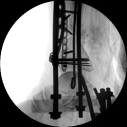

初步復(fù)位后X線